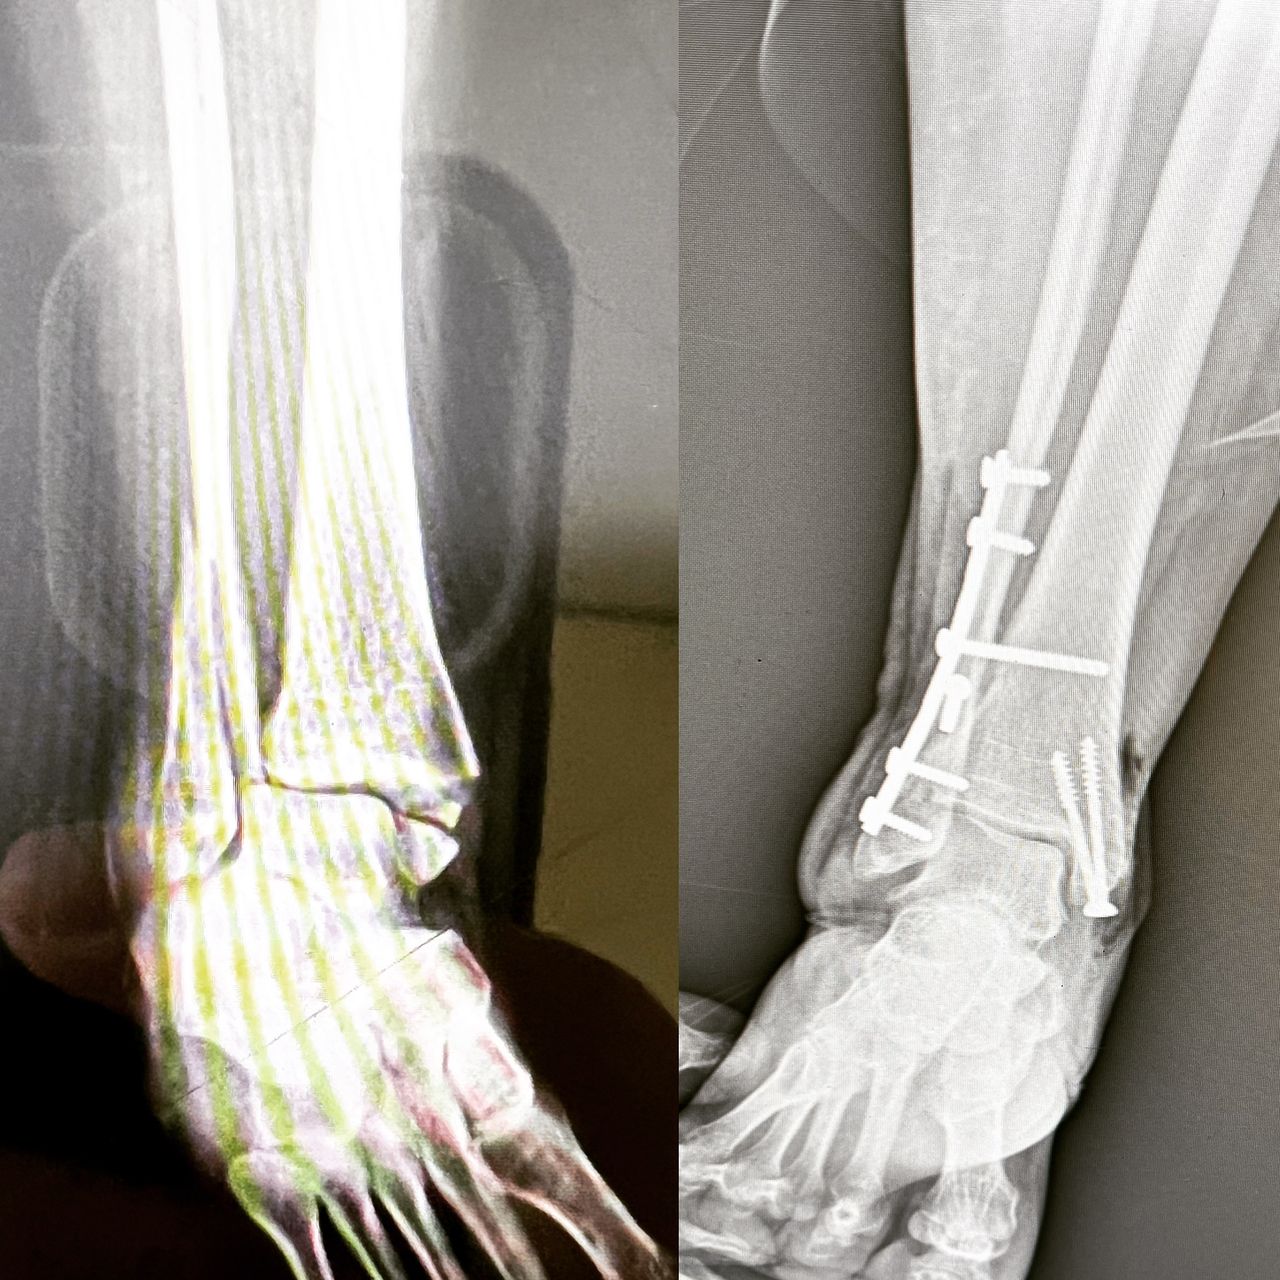

Fotos y videos